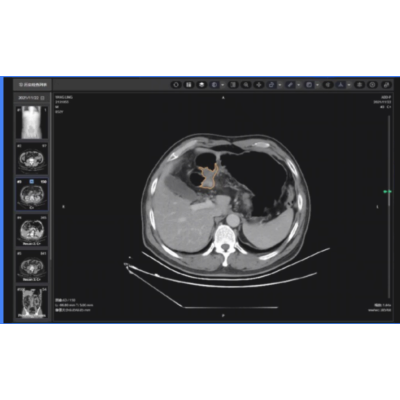

肺结节影像辅助分类诊断

精准识别、分割肺部各类结节灶,输出病灶定位、体积、倍增、密度、形态、征象等多元化参数,进行基于人工智能深度学习的病灶良恶性诊断,肺癌结节灶实现定性诊断。提供随诊复查功能系统,实现多次检查间病灶精准匹配,定量分析,帮助更方便地疾病监测、疗效评估。